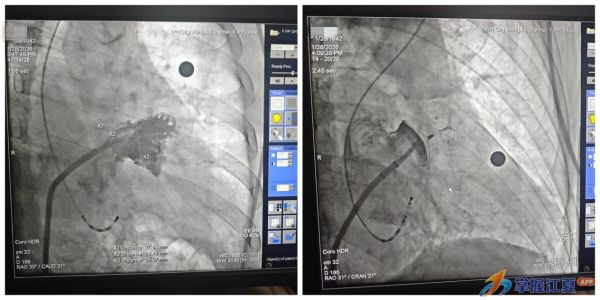

在对李爷爷的身体状况进行全面深入评估,并与家属充分沟通病情及手术方案后,手术顺利开展。心血管内科团队通过患者大腿根部的微小血管穿刺,将一枚特制封堵器精准送达心脏部位,在超声与X射线的精准“导航”下,封堵器如同一把微型“安全伞”,稳稳撑开并固定在左心耳入口,完美隔绝了左心耳与左心房的通道。整个手术创伤小、耗时短,术后影像显示,封堵器位置精准、固定牢固,无残余分流,手术取得圆满成功。